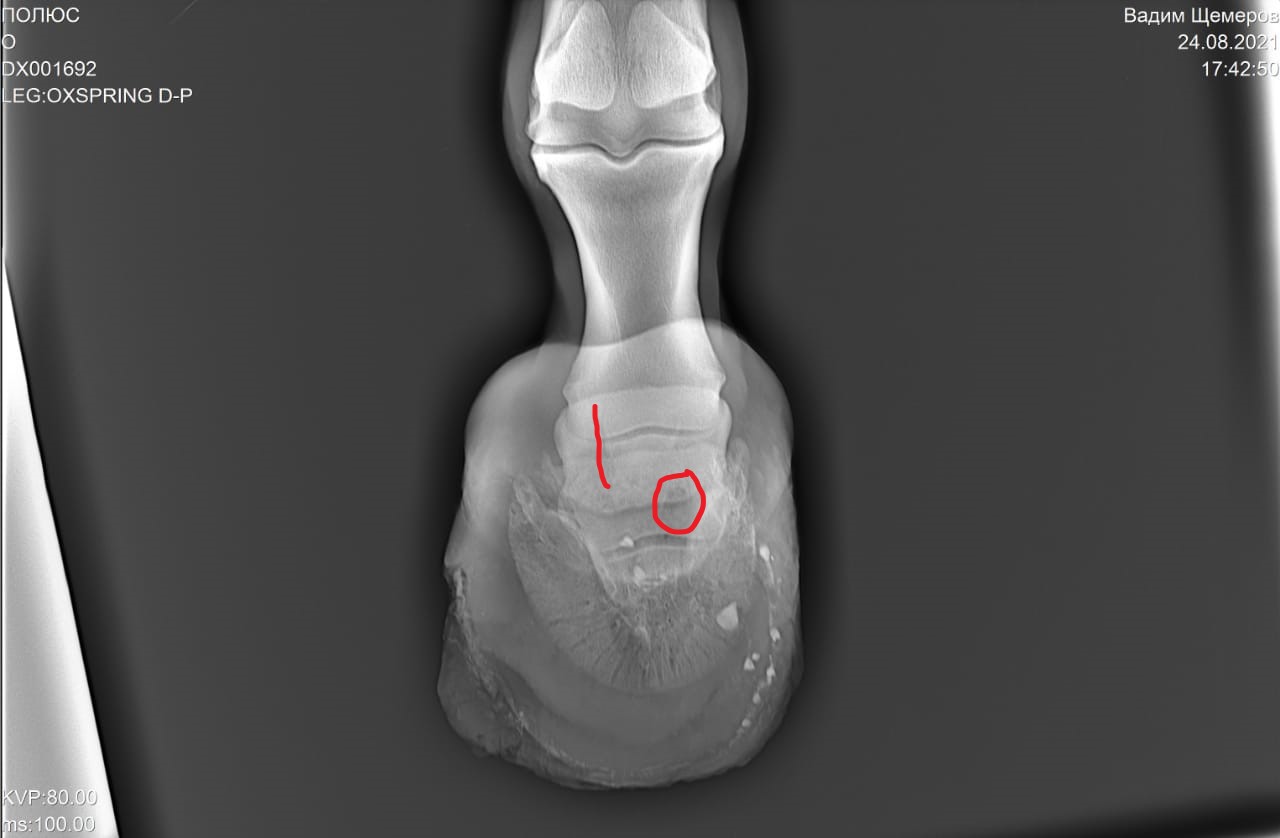

2) Старый перелом и изменение конфигурации края челночной кости с переостальной реакцией этого края.